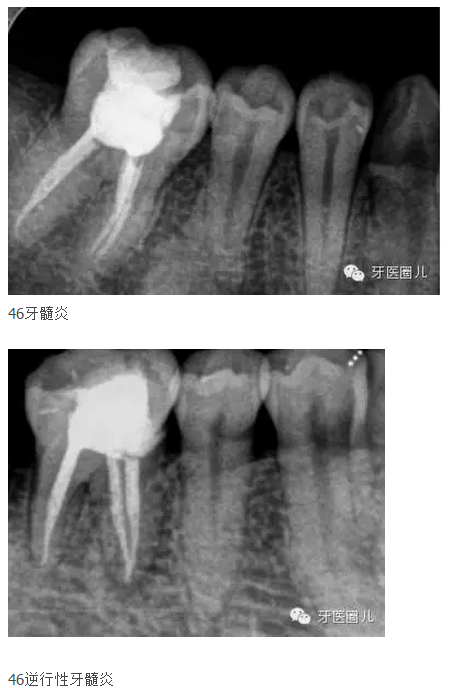

最后發(fā)兩張最近充的牙片

以上兩張是用不銹鋼k挫和G鉆預(yù)備,冷牙膠側(cè)方加壓充填的